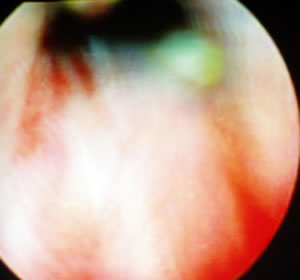

Затем оператор проводит цистоскопию, уретроскопию.

Увеличенная простата – аденома простаты.

Устья мочеточников были прикрыты гиперплазированной простатой.

В просвете мочевого пузыря видны два конкремента каждый

чуть больше 1 сантиметра.